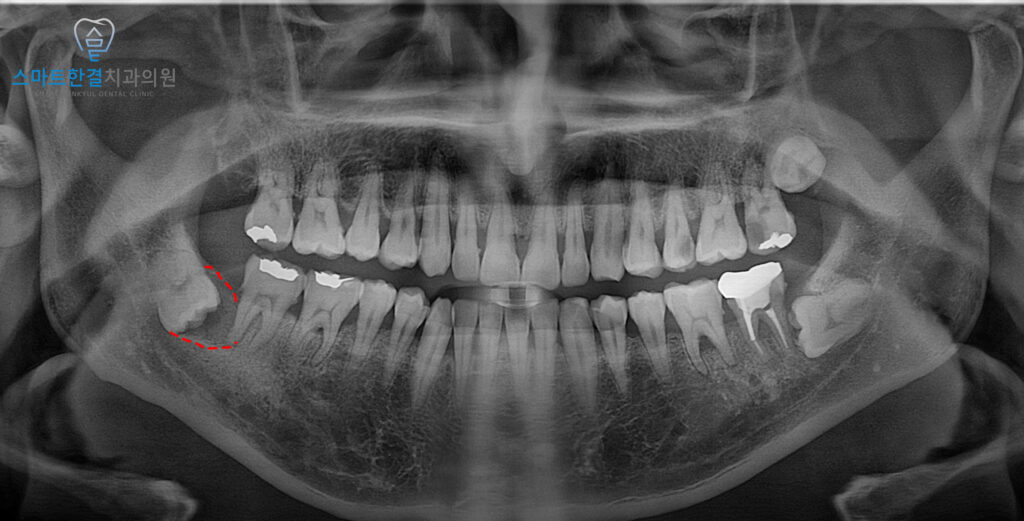

위 환자분께서는

아래쪽에 매복 사랑니가

존재하고 있었는데요.

첫 내원 당시에는 매복 사랑니 주변으로

특별한 통증이나 불편 증상이 없어

검진 후 경과 관찰하기로 하고

마무리 했어요.

이후 1년 뒤 검진 위해

재내원 해주셨어요.

파노라마를 촬영해 보니,

1년전보다 사랑니 주위로

방사선 투과상이 증가하고

앞 치아의 통증과 함께

이상한 맛이 느껴진다고 하셨는데요.